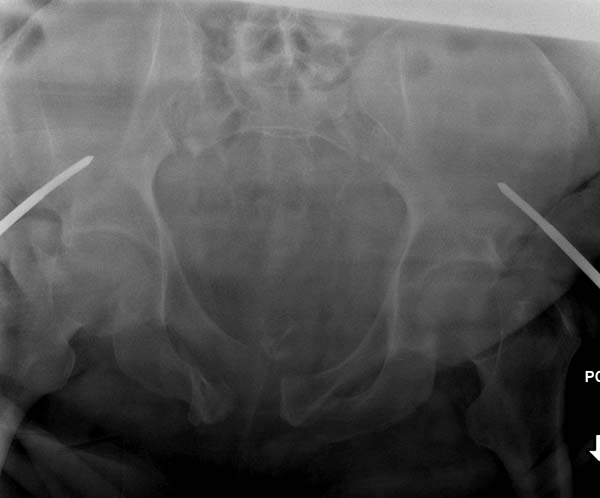

Двухстороннее повреждение крестца и травматическая ампутация бедра, где

неопытной бригадой дежурантов установлен верхний наружный фиксатор для

стабилизации. На третий день ревизия на более стабильный, и

окончательная фиксация. Первые снимки после стабилизации таза, и другие,